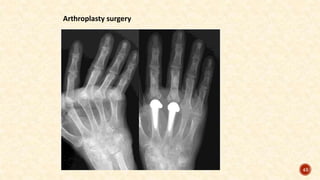

Arthroplasty surgery

4) TERMINAL, EROSIVE RA:

Reconstructive surgery

Reconstructive surgery is indicated when pain cannot be relieved by conservative

measures.

• Synovectomy (excision of the synovial membrane)

• Tenorrhaphy (suturing a tendon)

• Arthrodesis (surgical fusion of the joint)

• Arthroplasty (surgical repair and replacement of the joint).